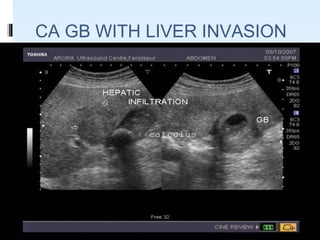

USG FINDINGS IN CA GB

 A Mass Completely Occupying Or Replacing The Gallbladder

Lumen

 Focal Or Diffuse Asymmetric Gallbladder Wall Thickening

 An Intraluminal Polypoid Lesion.

 Invasion of adjacent liver parenchyma

 Hepatic metastasis

 Periportal/ peripancreatic lymphadenopathy

 Sonographically : Heterogeneous, Predominantly Hypoechoic

Tumor Fills Much Or All of the gallbladder lumen.

CA GB WITH LIVER INVASION